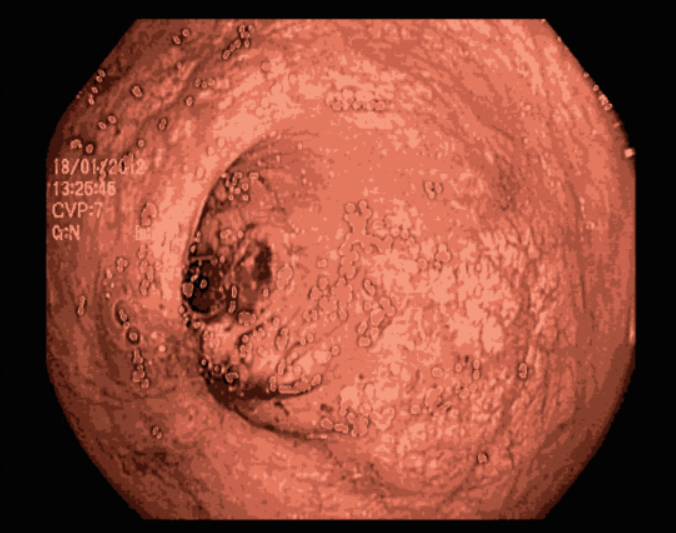

The data used to test this approach is the Kvasir dataset [35] which is a collection of annotated medical images of the gastrointestinal (GI) tract, designed for the purpose of computer-aided disease detection. The dataset is important for research in the medical domain of detection and retrieval, especially for single- and multi-disease computer aided detection. It contains images classified into three important anatomical landmarks and three clinically significant findings, as well as two categories of images related to endoscopic polyp removal. The sorting and annotation of the dataset are done by medical doctors. The Kvasir dataset may improve medical practice and refine health care systems globally since it includes sufficient numbers of images to be used for different tasks such as machine learning, deep learning, image retrieval, and transfer learning. The Kvasir dataset is collected using endoscopic equipment at Vestre Viken Hospital Trust in Norway and is carefully annotated by medical experts from VV and the Cancer Registry of Norway (CRN). The CRN is responsible for the national cancer screening programmes with the goal to prevent cancer death by discovering cancers or pre-cancerous lesions as early as possible. The Kvasir dataset is containing 8 classes of 2000 images per class. As a first step we opted to work with binary classification by feeding the model with both the normal images and the images having the disease.

5.2 Inpainting and clustering

One major issue our data had is the the endoscopic camera’s light in work. In order to tackle this problem we tried firstly to inpaint the images. We have considered the areas with light on them as having missing values, so the inpainting idea, which is the task of reconstructing missing regions in an image, comes into play. It is an important problem in computer vision and an essential functionality in many imaging and graphics applications, e.g. object removal, image restoration, manipulation, re-targeting, compositing, and image-based rendering. The technique consisted of finding the white pixels in the images and dilute the surrounding pixels using a certain threshold on the pixels’ values by working with a mask between 221 and 255, in order to conserve the maximum amount of information. After inpainting the images, we noticed that they still contain some noise in them. So in order to tackle this problem, we tried kmeans [55] for clustering. Clustering algorithms are unsupervised algorithms, meaning they don’t use labelled data. They are used to assign data points from a population to different groups where data points belonging to the same group have similar traits. In our instance, clustering the image enabled us to blend the several image segments together in order to lessen the noise that persisted even after the inpainting.